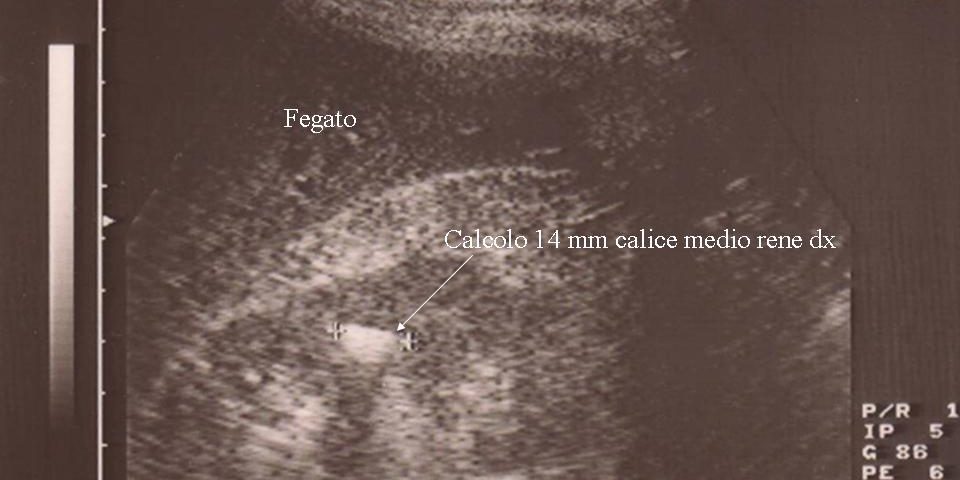

Calcolo Ø 14 mm del gruppo caliceale medio del rene destro

Ecografia Pre-litotrissia